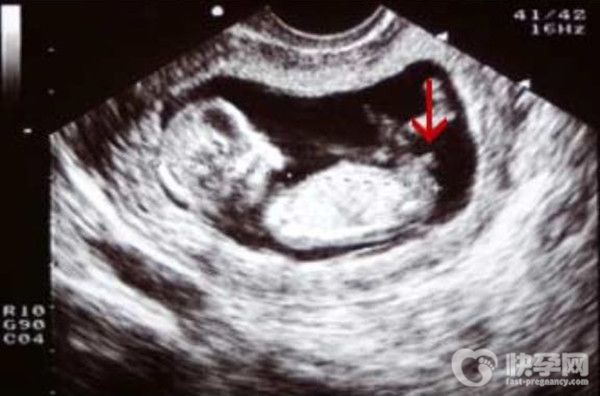

1.角度,主要是看nt全景的尾椎。只要特征点与身体成30度角,中间的角度非常明显,就证明是男孩;点几乎和身体平行没有角度,就是女生。

2.生殖器标志主要看男孩女孩的生殖器部位。我们都知道,男女最大的区别就是生殖部位不同。男生是明显的小疙瘩,亮点,像小JJ一样的小东西;女生两腿之间是平的,就是女宝宝的***。